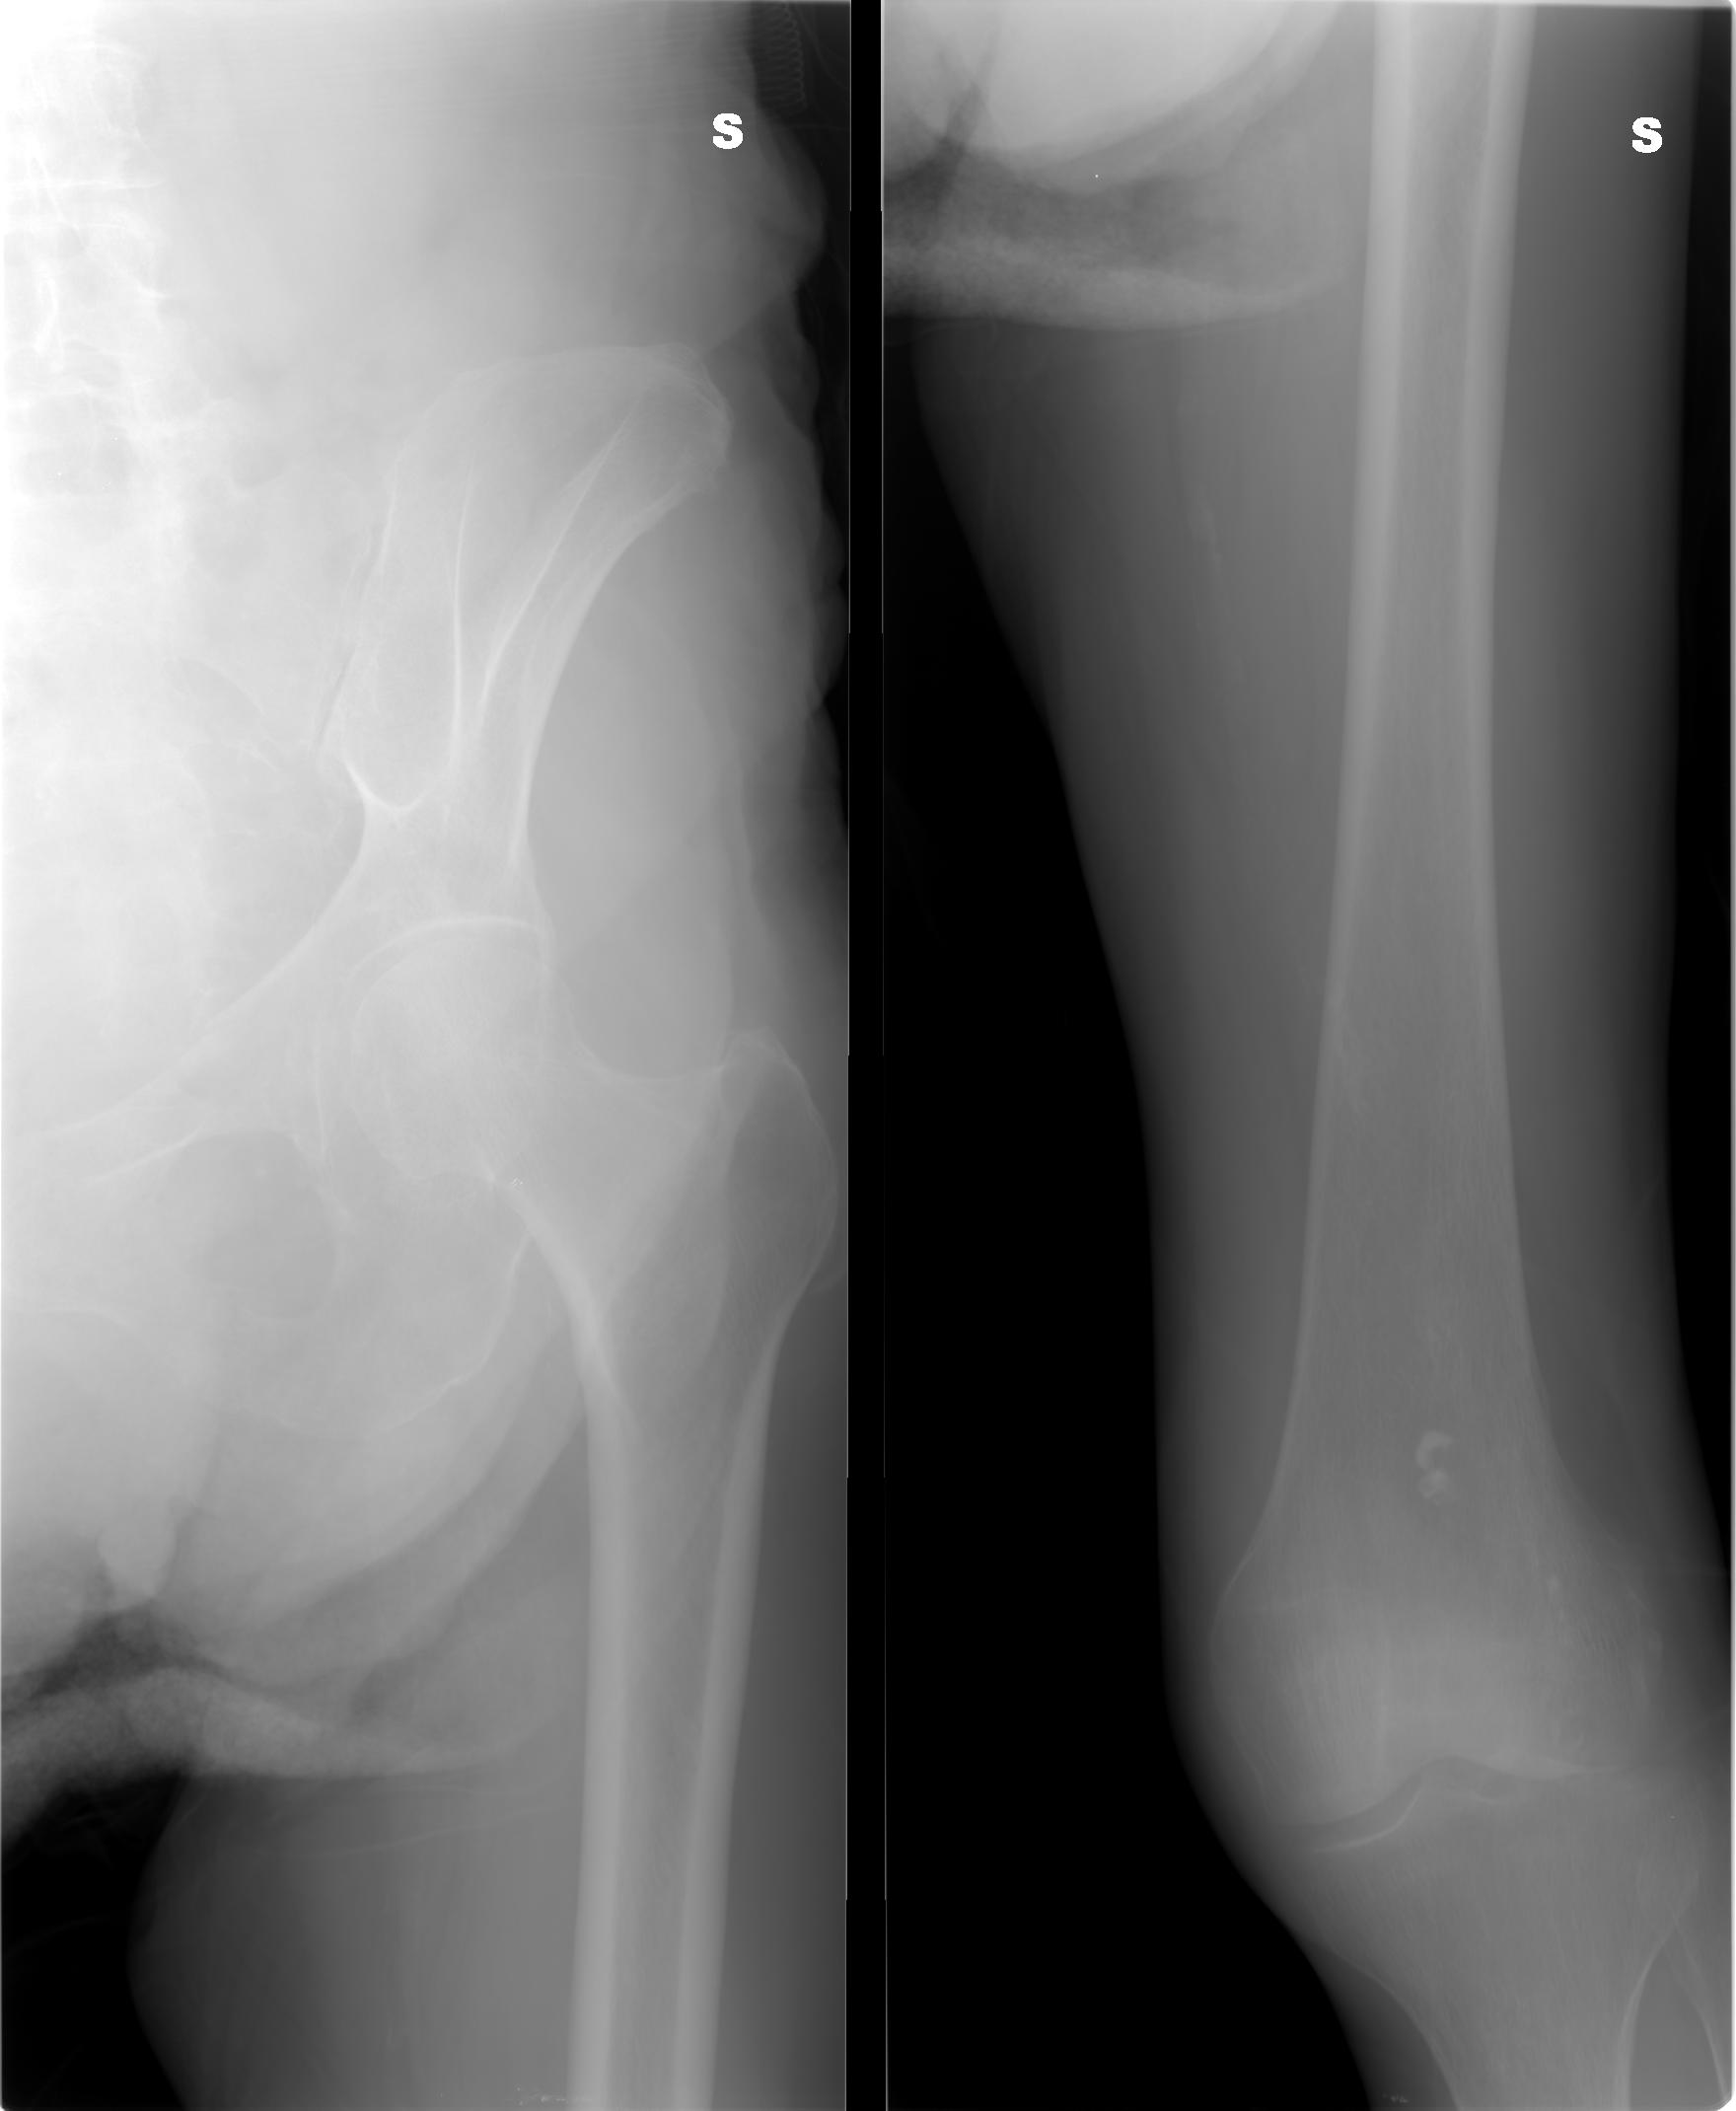

SALVE, ho ritirato un referto lastra per mia madre 80 anni e dice le seguenti parole: per quanto apprezzabile nel radiogramma a disposizione si osserva frattura composta della branca ile pubica sinistra .Sospetta frattura (o esiti fratturativi?) a carico dell branca ischio pubica omolaterale.

allego le lastre potete consigliarmi?